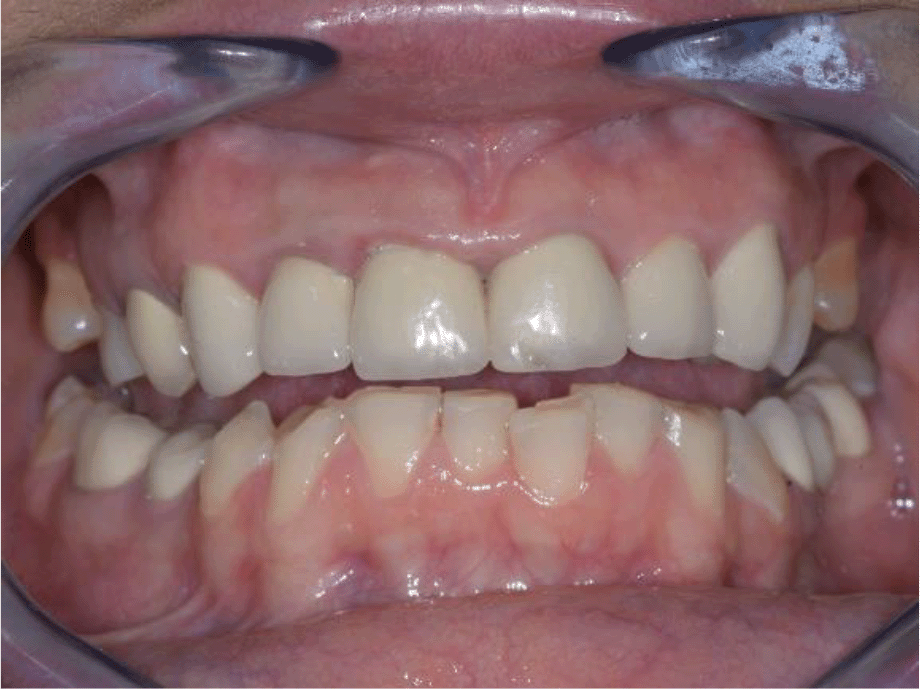

A 35-year-old female patient, Bulgarian restaurant owner, sought help due to impaired aesthetics, as a result of abraded tooth surfaces and severe symptoms of the right TMJ.

Intraoral examination of the upper jaw revealed a metal-ceramic construction on 13, 12, 11, 21, 22, 23, 24, missing 18, 16, 25, 26. The metal-ceramic construction was made 13 years ago, and was in good condition except for small fractures of the ceramic on the palatal surface and palatal staining of the gingiva by the metal base. The distal available teeth were medialized (Figures 1 and 2).

On the lower jaw, an advanced phase of abrasion (Attritio dentis cum abrasione) of the frontal teeth was established, reaching the dentin area. Defects of the dentitions were solved with ceramic restorations of 35, 36, 37 on the left and 45, 46 on the right. The occlusal plane was incorrect – the lower frontal teeth were higher. There was a deep overlap of the lower frontal teeth in central occlusion (Figures 3 and 4).

26dd931c-41d3-478d-bec1-8cb211d0a4b8_figure3.gif

Figure 3. Abraded lower teeth and occlusal plane at initial presentation.

26dd931c-41d3-478d-bec1-8cb211d0a4b8_figure4.gif

Figure 4. Central occlusion shown on initial presentation.

During palpation of the TMJ, the patient responded with mild pain on the right side.